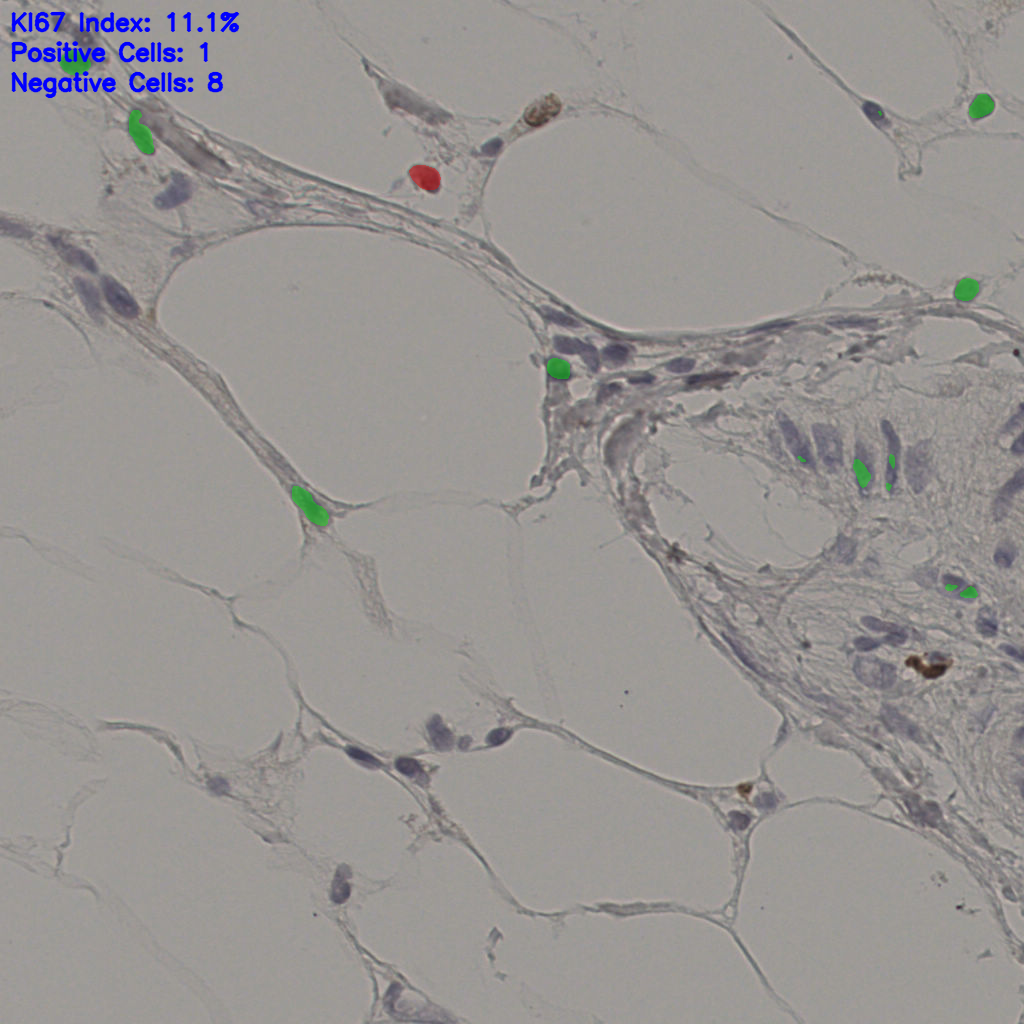

17.75%

Ki67 指数

阴 7986 阳 1723

总切片 2640

有效 412

已标记 412

有效率 16%